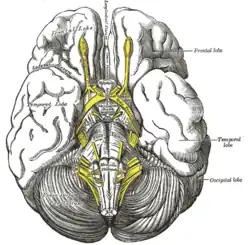

The fornix and corpus callosum from below.